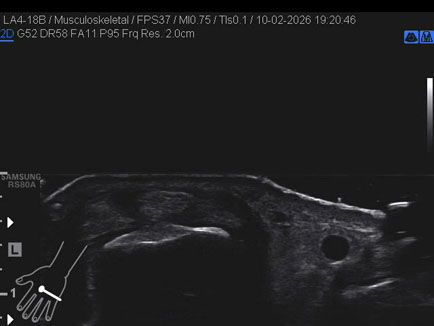

Data inserimento: 13/02/2026

Ecografia del: 10/02/2026

Strumento: Samsung

Sonda: Lineare

Commento all'esame: rottura della bandelletta laterale MTC-F del II° dito con conseguente lussazione del tendine estensore.

Conclusioni: rottura della bandelletta laterale metacarpo-falangea del 2° dito della mano sinistra (tear of the lateral band of the metacarpophalangeal - MCP - joint of the left index finger).

Realizzazione: Dr. F. Pietro Tarini - Gubbio (PG)